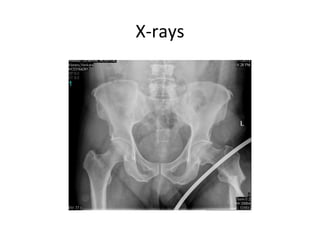

X-rays

Subtrochenteric femur fracture

• Subtrochanteric area typically defined as area

from lesser trochanter to 5cm distal.

• fractures with an associated intertrochanteric

component may be called intertrochanteric

fracture with subtrochanteric extension or

peritrochanteric fracture